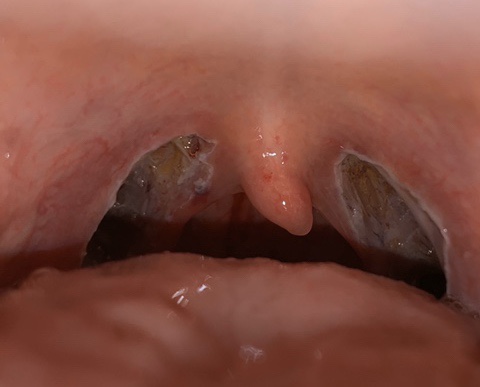

첫째날 검은부분이 사라지고 하얀막같은게 생겼어!! 이날부터 아픈데..나는 솔직히 퇴원 후 일주일 후가 제일 아팠어.

3일째 흰부분이 전체적으로 적어진 느낌!진통제하러 병원도 가다

4일째 회복력이 너무 좋다고 느낀 4일째! 회복이 눈에는 보이지만 아팠다.약도 가루약 먹다가 흰 부분을 다쳐서 죽는다.

5일째에 벌써 하얀 부분이 많이 사라졌다.요즘부터는 매일 엉덩이주사를 맞을 정도로 아팠어ㅜㅜ